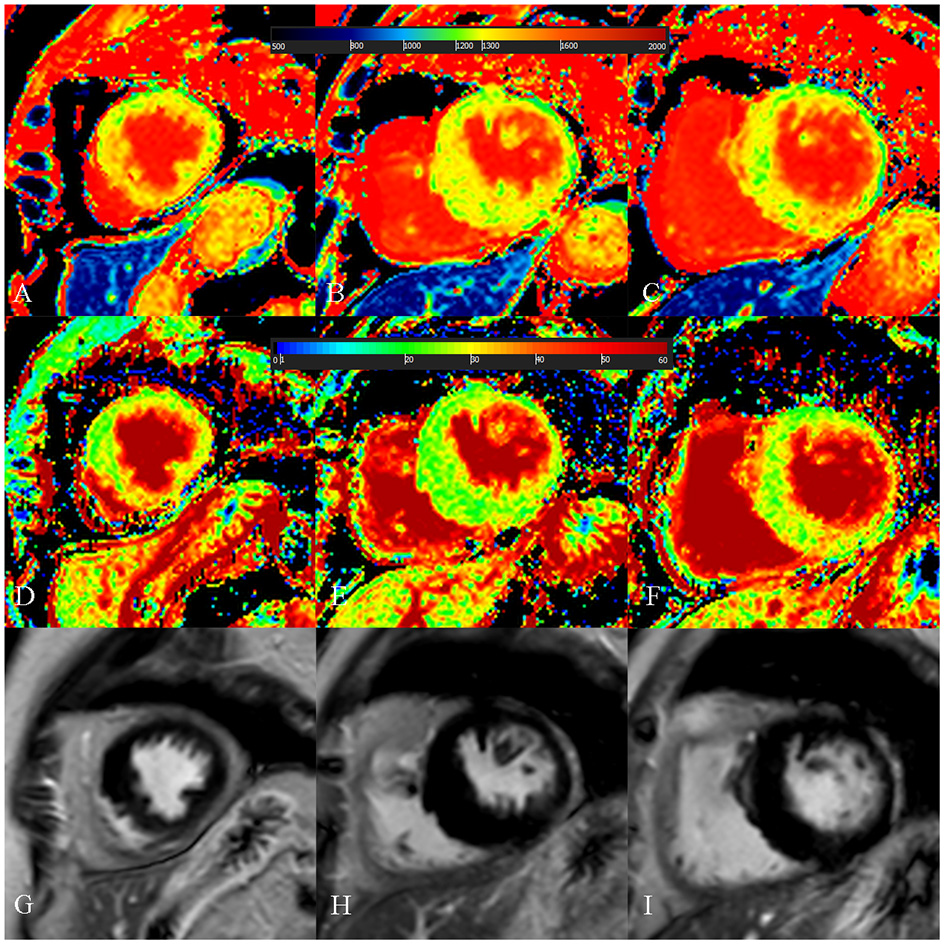

Figure 5

A 73-year-old female with focal midseptum hypertrophic cardiomyopathy. (A–C) Native T1 mapping of the apical, mid-, and basal portions of the left ventricular (LV) myocardium showed increased global native T1 (1,335.03 ms). (D–F) Extracellular volume fraction (ECV) of the apical, mid-, and basal portions of the LV myocardium showed normal global ECV (26.9%). (G–I) Late gadolinium enhancement (LGE) images of the apical, mid-, and basal portions of the LV myocardium showed no LGE. The maximal LV wall thickness was 19.8 mm, left atrial diameter was 40 mm, and the LV outflow tract gradient pressure was 95 mmHg. She had no family history of sudden cardiac death (SCD), non-sustained ventricular tachycardia, unexplained syncope, LGE/LV mass ≥15%, end-stage systolic dysfunction, and apical aneurysm. She was stratified as having low SCD risk under the 2014 European Society of Cardiology guidelines (5-year SCD probability: 1.70%) and enhanced American College of Cardiology/American Heart Association guidelines. However, she underwent cardiac-caused death 26 months after cardiac MRI examination. The elevated global native T1 mapping values could help indicate poor outcome in patients with low risk according to the two guidelines.